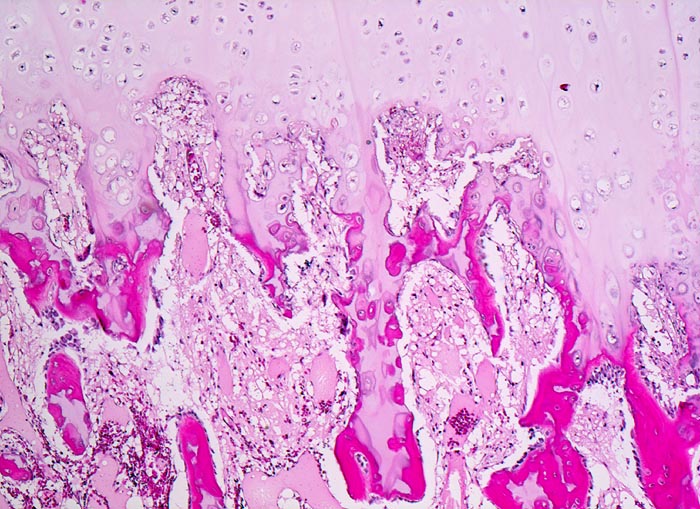

Osteochondrom: Enchondrale Ossifikation

Übergang der hyalinen Knorpelkappe in den knöchernen Stiel über eine enchondrale Ossifikationszone. Die verkalkte Knorpelgrundsubstanz wird teilweise abgebaut und durch Osteoid ersetzt. Das Osteoid wird gebildet von zahlreichen Osteoblasten, welche dem neugebildeten Knochen aufsitzen.

Geringe, gelegentlich mechanisch störende schmerzlose Schwellung an der Innenseite des Oberschenkels kurz oberhalb des Knies.